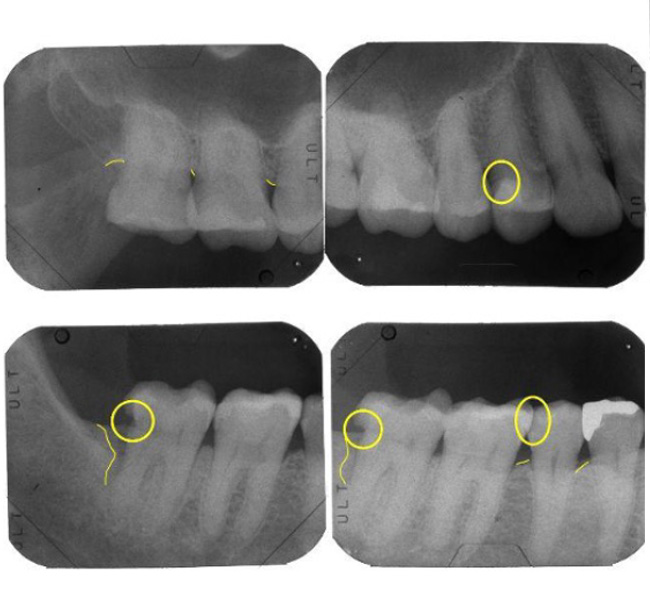

治療前(デンタルX線写真)

※クリック(タップ)で拡大します

治療後(デンタルX線写真)

経過

(デンタル)

【デンタル】

抜歯から1年半後の経過

抜歯と同時に行った「リッジプリザベーション(歯槽骨保存術)」により、建物の土台となる地盤(歯槽骨)が理想的な形で維持されています。通常、抜歯後は地盤沈下のように骨が痩せてしまいますが、適切な処置によって吸収は認められません。

この期間、他の部位の「基本治療」も着実に進行しました。隣の歯(左下5番)には、精密なプレスセラミックによる新しい修復を施行。以前の暫定的な詰め物(CR修復)では対応しきれなかった複雑な形態も、高い適合精度で再構築され、細菌の侵入を許さない強固な構造へと生まれ変わっています。

【精密検査】基本治療後の精密検査(再評価)

再評価と「予防会員制度」の重要性

精密なセルフコントロールトレーニングとSRP(歯石除去)を重ねた結果、お口全体の数値は劇的に改善しました。しかし、右下の一番奥(7番)の遠心側には、依然として6mmの深い数値が残存していました。

右下7番への精密外科手術

細菌コントロールを万全に整えた(BOPマイナス)後、構造的に残ってしまった6mmのポケットに対し、ウィドマン改良型フラップ手術を施行しました。

【精密検査】外科治療後の精密検査(再評価)

術後の精密検査では、ポケットは3mmへと改善。炎症の再発(BOP)も一切認められず、地盤の安定が確認されました。これにより、ようやく「口腔機能回復治療(最終的な被せ物や義歯)」という最終建築フェーズへと進むための、揺るぎない土台が完成しました。